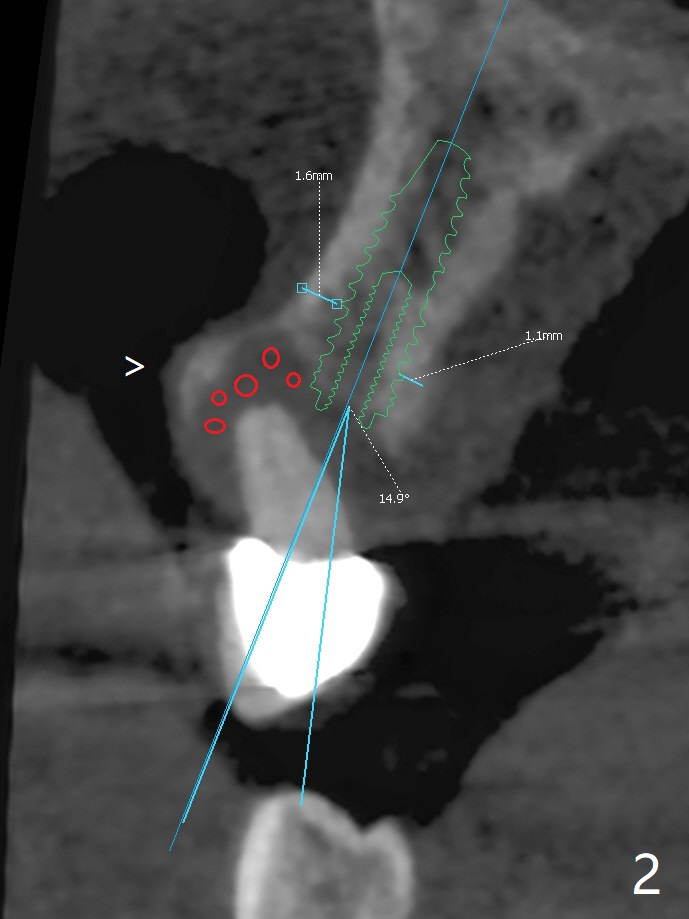

A 52-year-old man requests extraction of the mobile deciduous canine for implant (Fig.1). Use sticky bone (Fig.2 red) to maintain the canine prominence (>). In fact, there is apical perforation of the deciduous canine (Fig.3-5: *). Before bone graft, place a small piece of PRF for repair. The patient refuses to close the diastema between #8 and 9 (Fig.4 ^). Since the cancellous bone is 2.9 mm (Fig.3), it is safe to place a narrow implant (Fig.7). Return to Protect Graft Clindamycin 手术 15 Xin Wei, DDS, PhD, MS 1st edition 04/28/2021, last revision 05/27/2021